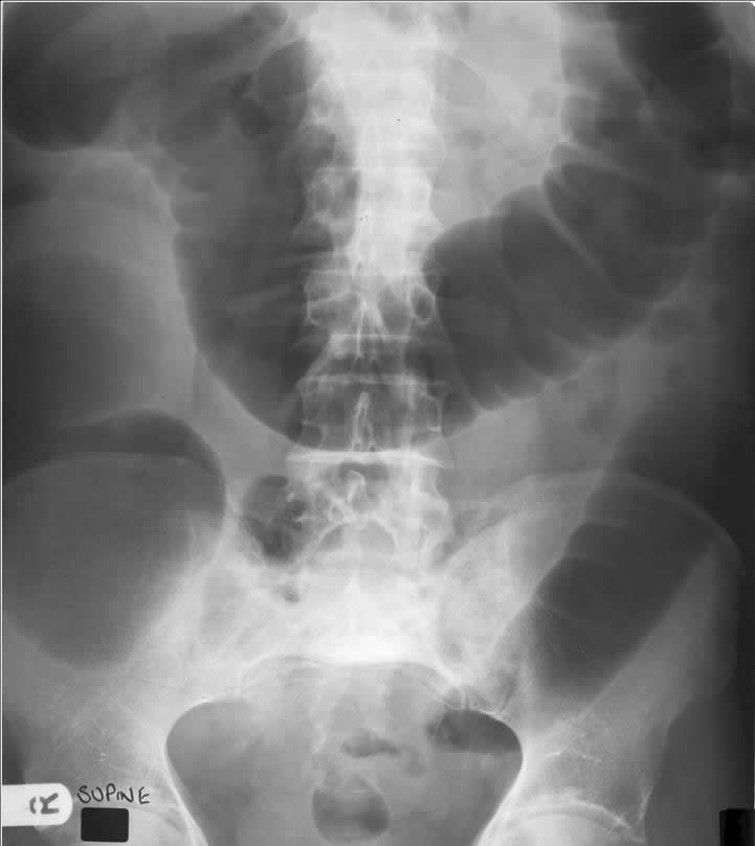

What is shown in the AXR?

Sigmoid volvulus